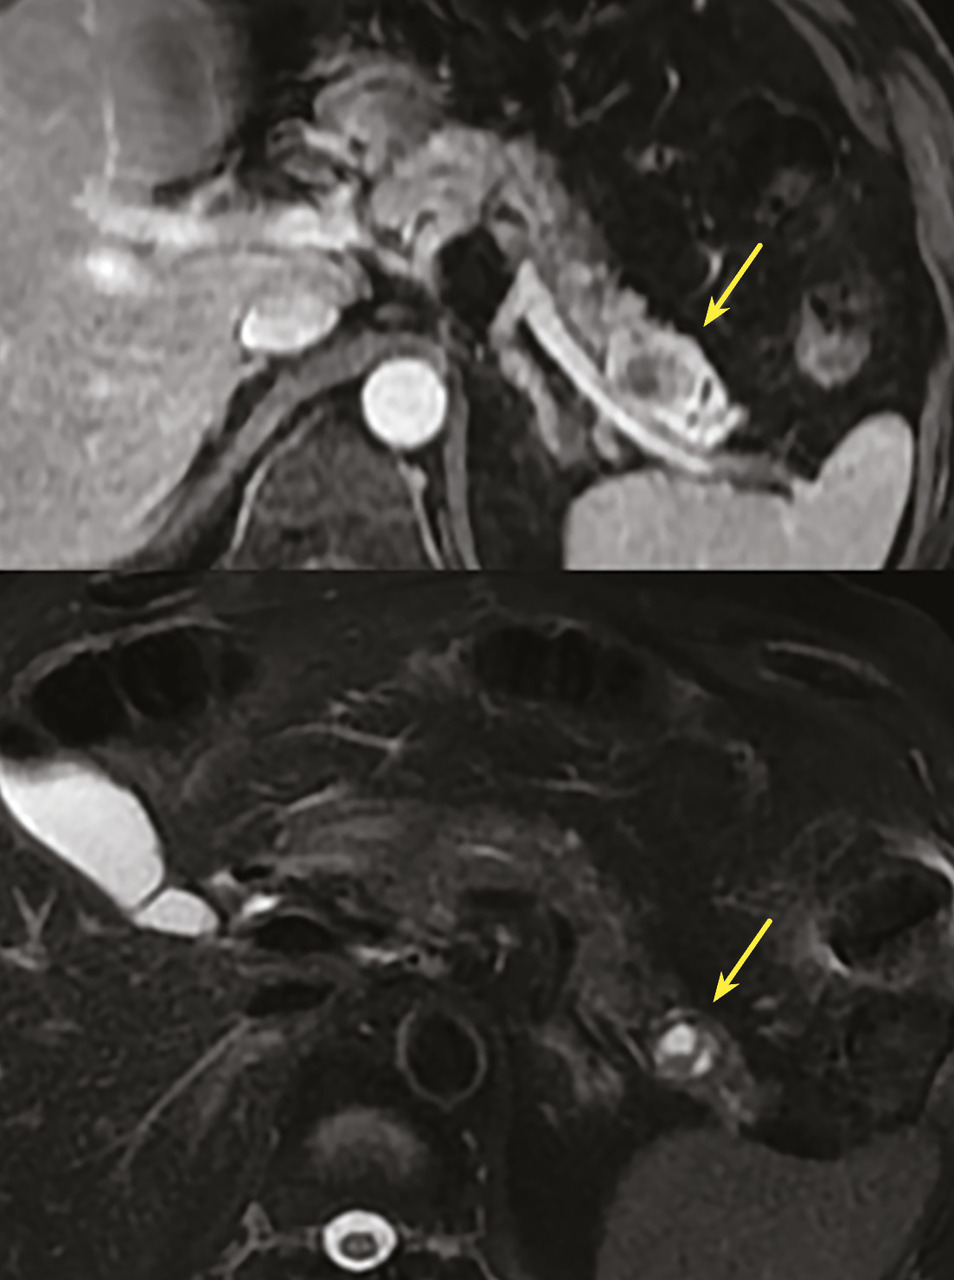

Toujours parmi les LKP rares à potentiel malin, on compte les tumeurs neuro-endocrines (TNE) kystiques (20 % des TNE pancréatiques) [fig. 5]. De découverte fortuite et non fonctionnelles, les TNE kystiques sont uniques, uniloculaires, bien différenciées, de bas grade, c’est-à-dire avec un indicateur de prolifération Ki67 < 3 %, et la présence d’une masse hypervasculaire (nodule) au niveau de la paroi. La partie charnue tissulaire peut être de petite taille.

La prise en charge a longtemps reposé sur une résection systématique des lésions, indépendamment de leur taille ou de leur grade. Des essais prospectifs européens sont en cours pour évaluer le risque de métastases ganglionnaires et à distance en cas de surveillance, pour ainsi valider (ou non) une attitude attentiste.

Selon l’âge et les comorbidités, on peut recommander de surveiller les TNE mesurant moins de 2 cm avec une imagerie en coupe (scanographie ou IRM) tous les six mois pendant dix-huit mois puis tous les ans. En cas de résection, une chirurgie d’épargne est à proposer pour les tumeurs mesurant moins de 2 cm.